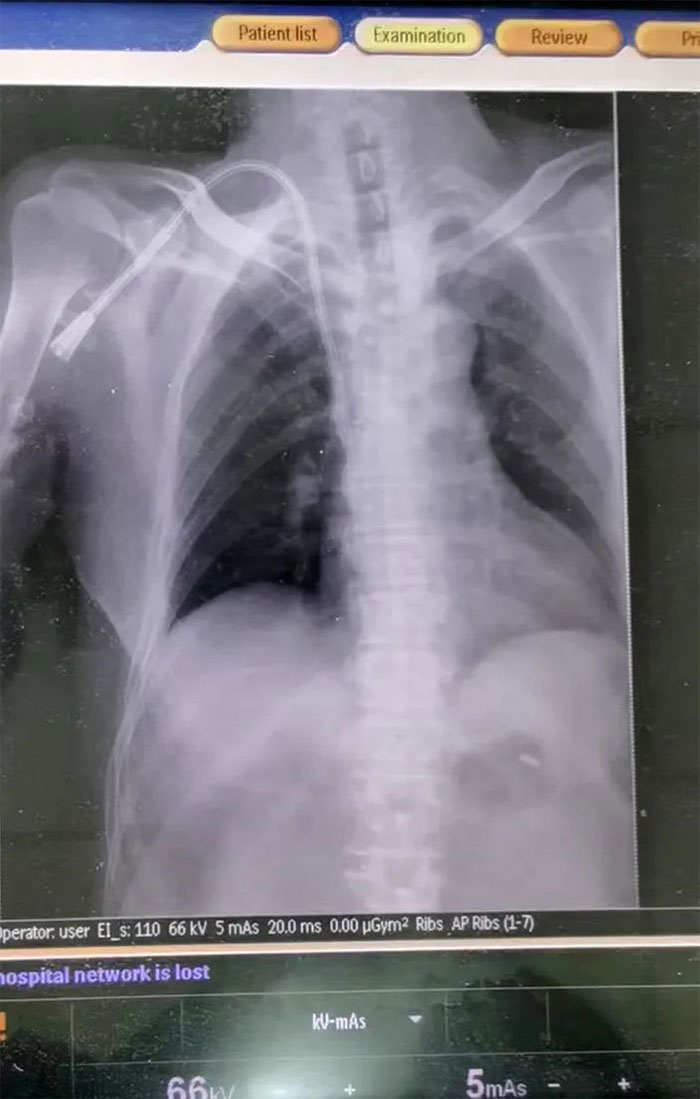

▲ DR驗證,導管已經到達指定部位

情況緊急,必須儘快為患者重新構建一條長期透析血管通路。為拯救患者,經醫護團隊反覆討論,與患者家屬充分溝通病情後,決定為患者行右鎖骨下靜脈長期導管置入術。在張慶成主任、李嚮明醫生及醫護團隊通力協作下,最終成功為該患者建立“生命通道”,架起生命橋樑。再經過DR驗證,導管已經到達指定部位,未出現出血等相關併發症及靜脈阻塞症狀,術後導管引血通暢,血液透析、輸血順利進行。